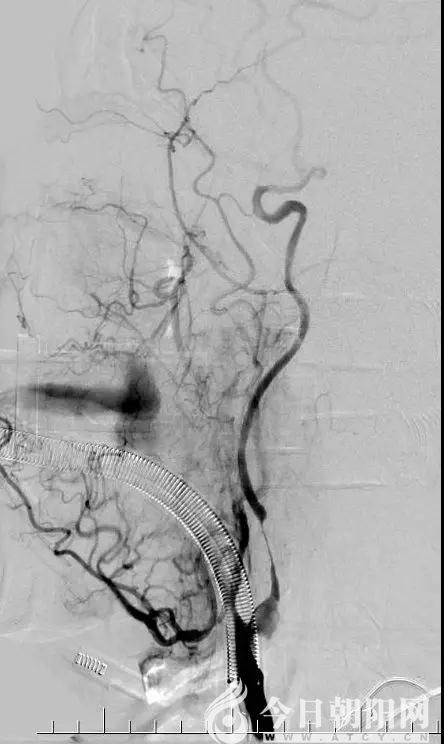

手術(shù)中發(fā)現(xiàn),患者的病變部位遠(yuǎn)比預(yù)想的病情要復(fù)雜得多,右側(cè)鎖骨下動脈近端閉塞、右側(cè)椎動脈閉塞、右側(cè)頸總動脈近端重度狹窄90%、右側(cè)頸內(nèi)動脈起始段已經(jīng)完全閉塞、遠(yuǎn)端的血管已經(jīng)完全不顯示。全腦血管造影后,前交通動脈也是不通的,這意味著患者的對側(cè)頸內(nèi)動脈對患側(cè)完全沒有代償,情況非常危急。經(jīng)家屬知情同意后,進(jìn)行了2次支架取栓,患者頸內(nèi)動脈起始段終于獲得了部分開通。

取栓后造影顯示頸內(nèi)動脈為通暢,但仍有嚴(yán)重狹窄,應(yīng)用藥物防止再次閉塞。